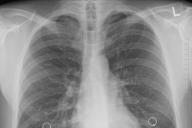

легкие

Снижение иммунитета примело к тому, что поведение подопытных мышей после ИВЛ вернулось в норму.